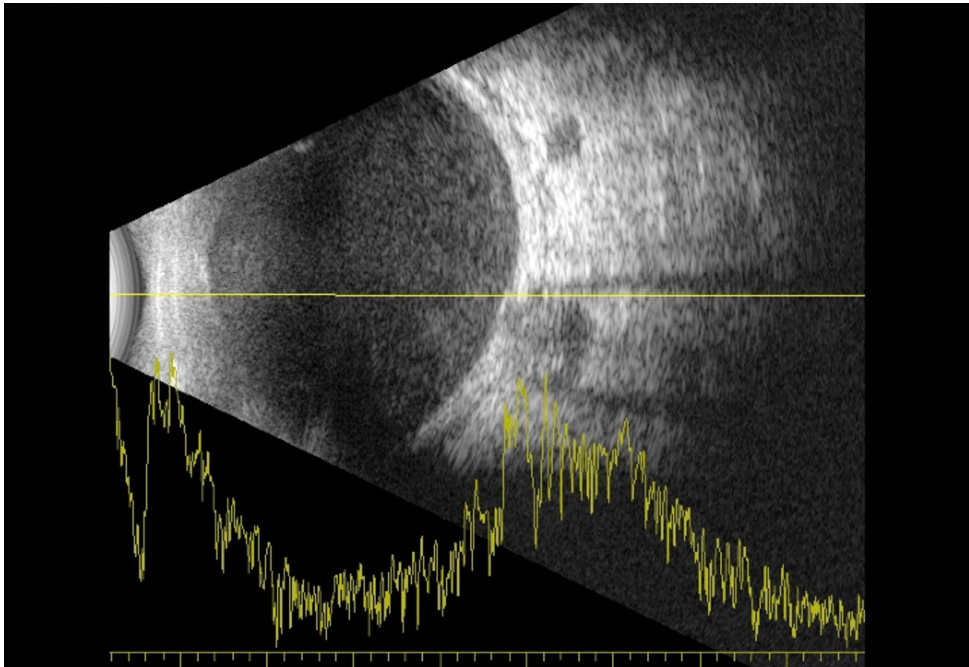

研究团队采用了多项关键技术:在疑似眼球穿孔后立即进行B超检查评估视网膜状态;确诊眼内炎后24小时内实施紧急PPV手术;术中采集玻璃体液进行革兰染色和培养;应用眼内激光(endolaser)封闭注射部位;注入硅油维持眼内结构;术后3个月进行硅油取出联合视网膜前膜剥除。值得注意的是,患者因原发性肾上腺功能不全长期使用糖皮质激素,这种免疫抑制状态可能是诱发感染的重要因素。

病例展示:患者注射后出现结膜下出血,B超未见视网膜脱离;一周后出现眼痛、畏光,检查发现前房3+细胞,玻璃体严重混浊。